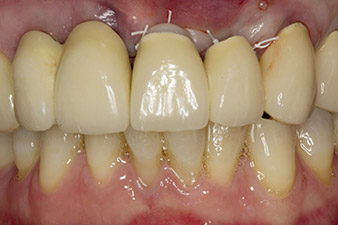

Dans cette étude de cas, le problème a trouvé sa solution avec la pose d'un implant en position 22 lors de la première intervention et d'un implant supplémentaire à l'endroit de la dent extraite 23 à un stade ultérieur du traitement. Le second implant a été posé une fois l'ostéointégration complète de l'implant 22 réalisée. Après retraitement, le bridge a été remis en place jusqu'à la cicatrisation de l'implant 23 en place et la formation complète de la restauration définitive. Cette approche par étapes a pour avantages que les implants tolèrent mieux les charges et les tissus durs et mous matures (5).